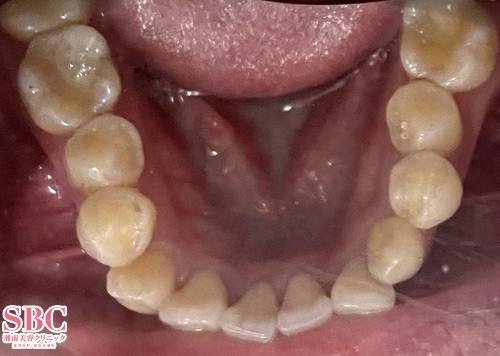

施術前

施術後12ヶ月後

インビザラインGOで治療されたお客様です。12か月の矯正で改善しています。※お客様の着用日数により、完成時期が前後します。マウスピース矯正は医師の設計とお客様が装着時間をお守りいただくことで良い結果が得られます。お客様、マウスピース矯正お疲れ様でした^^

インビザラインGOで治療されたお客様です。

12か月の矯正で改善しています。

※お客様の着用日数により、完成時期が前後します。

マウスピース矯正は医師の設計とお客様が装着時間をお守りいただくことで

良い結果が得られます。

お客様、マウスピース矯正お疲れ様でした^^